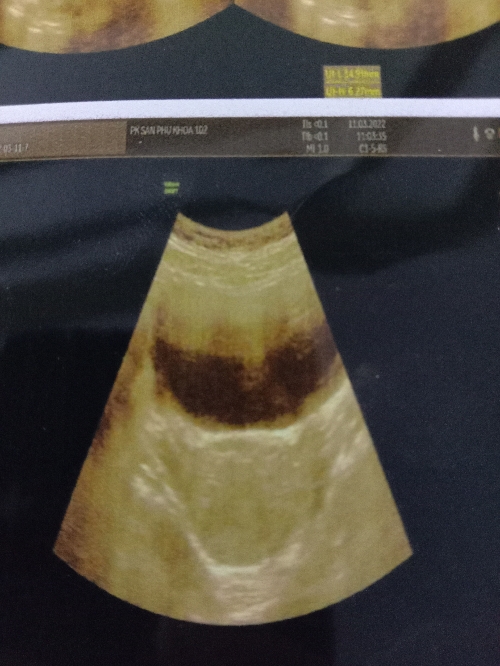

Em siêu âm bụng dưới thì kết quả nhìn giống có túi thai nv ạ em k biết phải thai hay k ạ